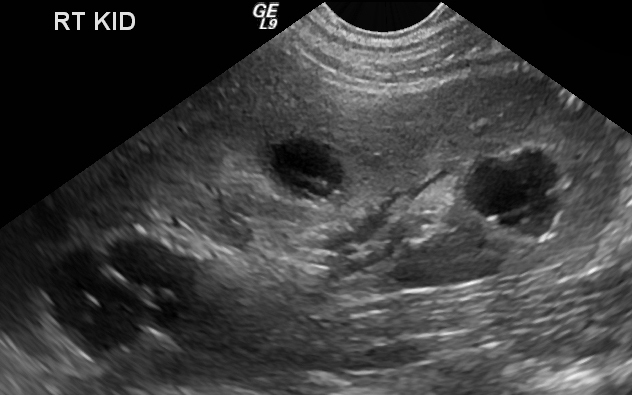

Complicated Cysts

Case courtesy of Dr Ian Bickle, Radiopaedia.org, rID: 24244